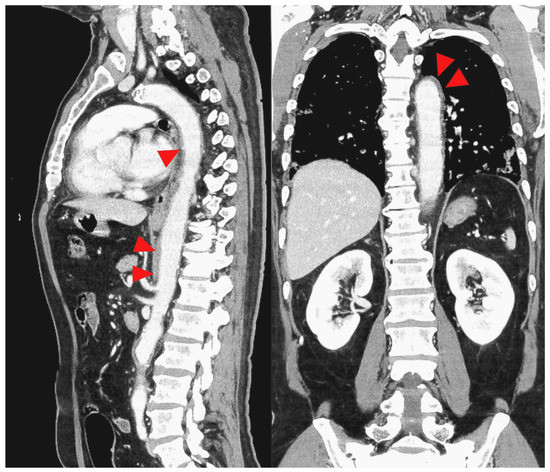

2. Case Presentation

| Shimada et al. (this case) | M | 65 | HTN | Fever and right cervical pain | 3 weeks | Aortic arch to right common carotid artery and right internal carotid artery | CT | 280 | 63 | 18.3 | 24 | None | 11 days | - | Discharge |